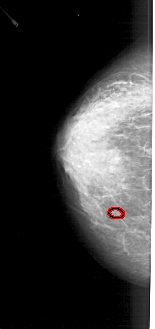

FILE: A_1280_1.LEFT_CC.OVERLAY

TOTAL_ABNORMALITIES 1

ABNORMALITY 1

LESION_TYPE CALCIFICATION TYPE PLEOMORPHIC DISTRIBUTION CLUSTERED

ASSESSMENT 4

SUBTLETY 2

PATHOLOGY BENIGN

TOTAL_OUTLINES 1

LEFT_CC LINES 4606 PIXELS_PER_LINE 2161 BITS_PER_PIXEL 12 RESOLUTION 43.5 OVERLAY